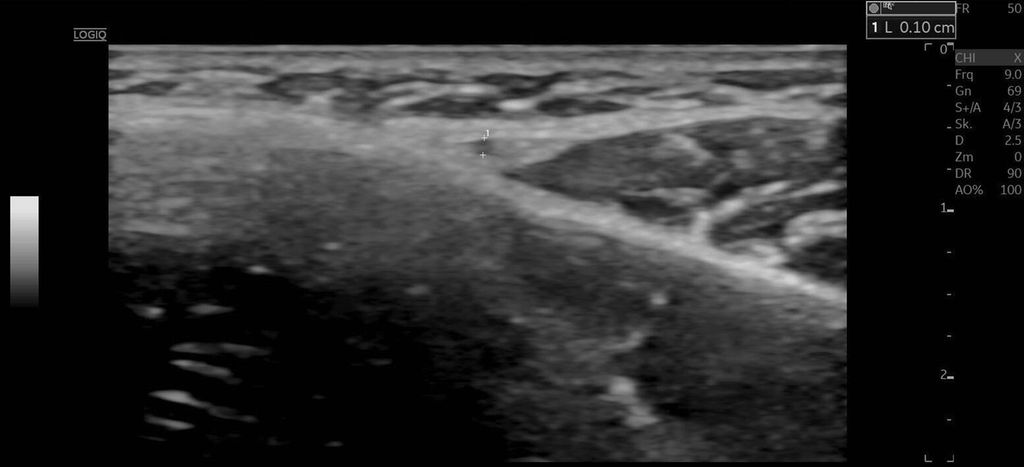

Die A. facialis imponierte beim Austritt im Bereich des Musculus masseter (oberhalb der Kieferlinie) vasospastisch mit einem maximalen Durchmesser von 1mm. Die abgeleitete systolische Spitzengeschwindigkeit betrug trotz der bestehenden Ischämie 20cm/s, ohne enddiastolische Komponente, was auf eine weitere periphere Vasokonstriktion hindeutete (Abb. 2 und 3).